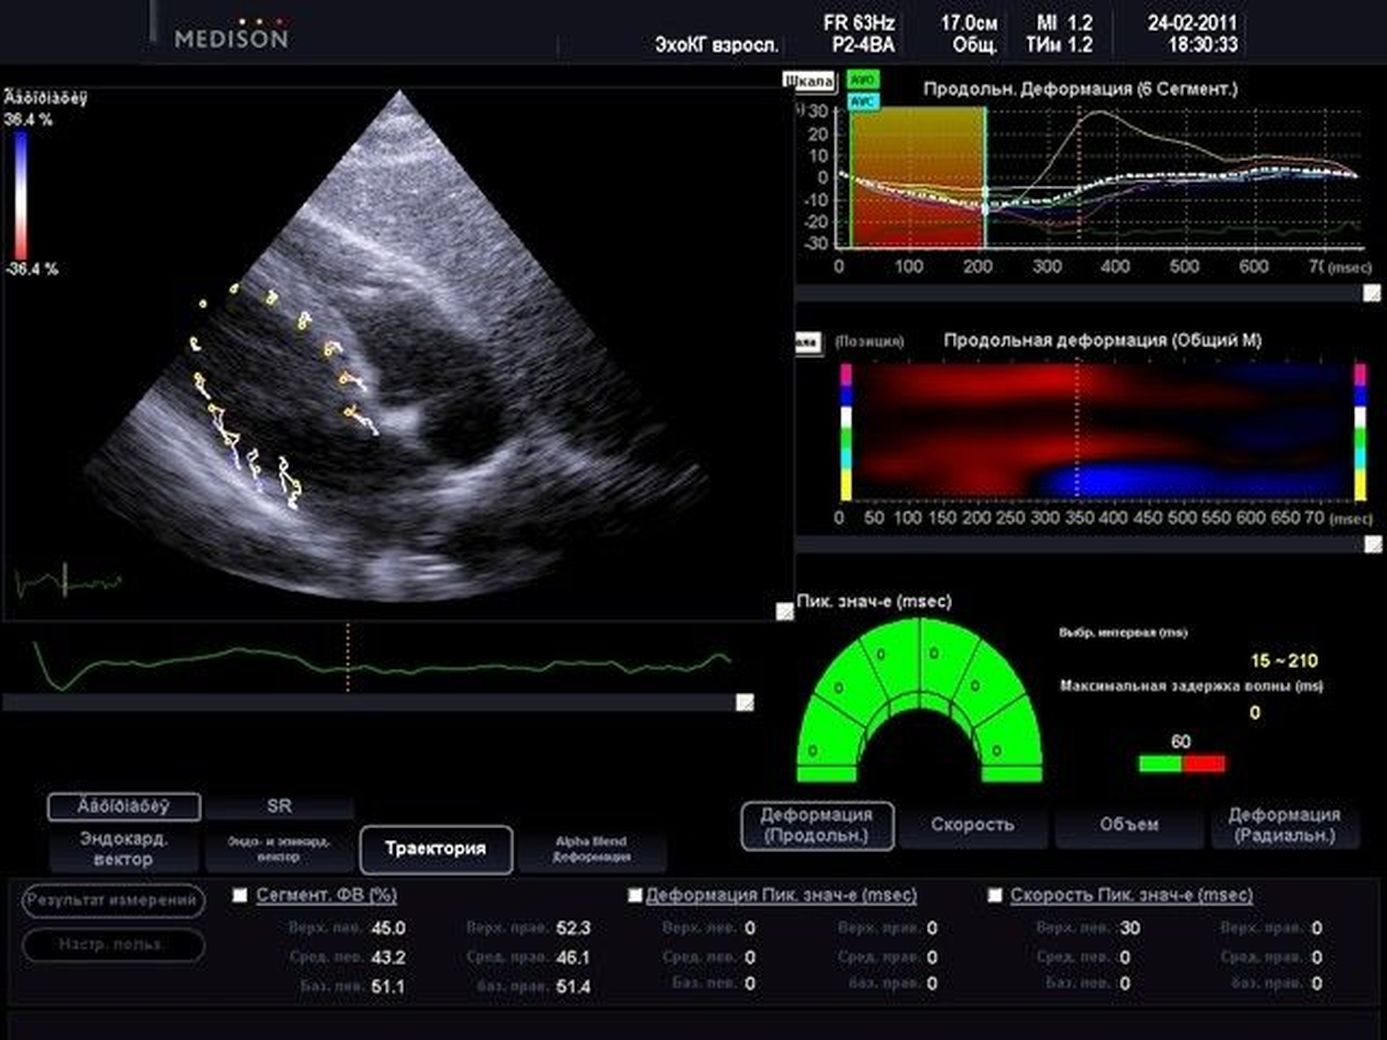

льный стрейн

Продольный стрейн 105 фото